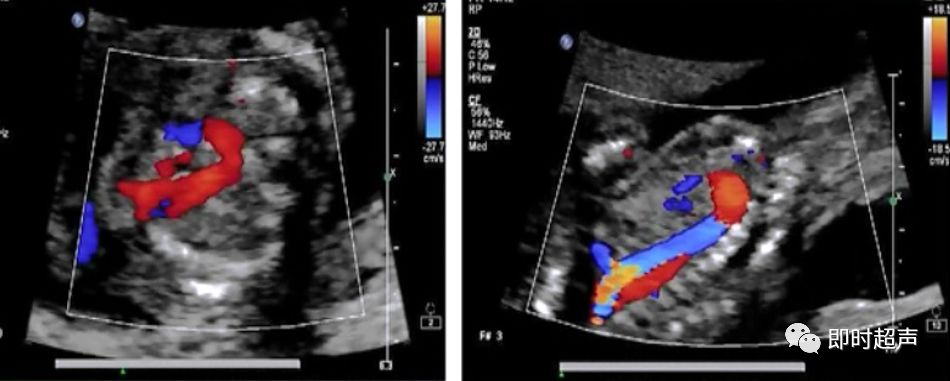

五、血流方向的异常

主动脉弓或肺动脉血流方向相反是导管依赖型心脏畸形的典型表现

主动脉弓血流反向

左心发育不良综合症(二尖瓣或主动脉瓣闭锁或重度狭窄)

肺动脉血流反向

右心发育不良综合症(三尖瓣或肺动脉瓣闭锁或重度狭窄)